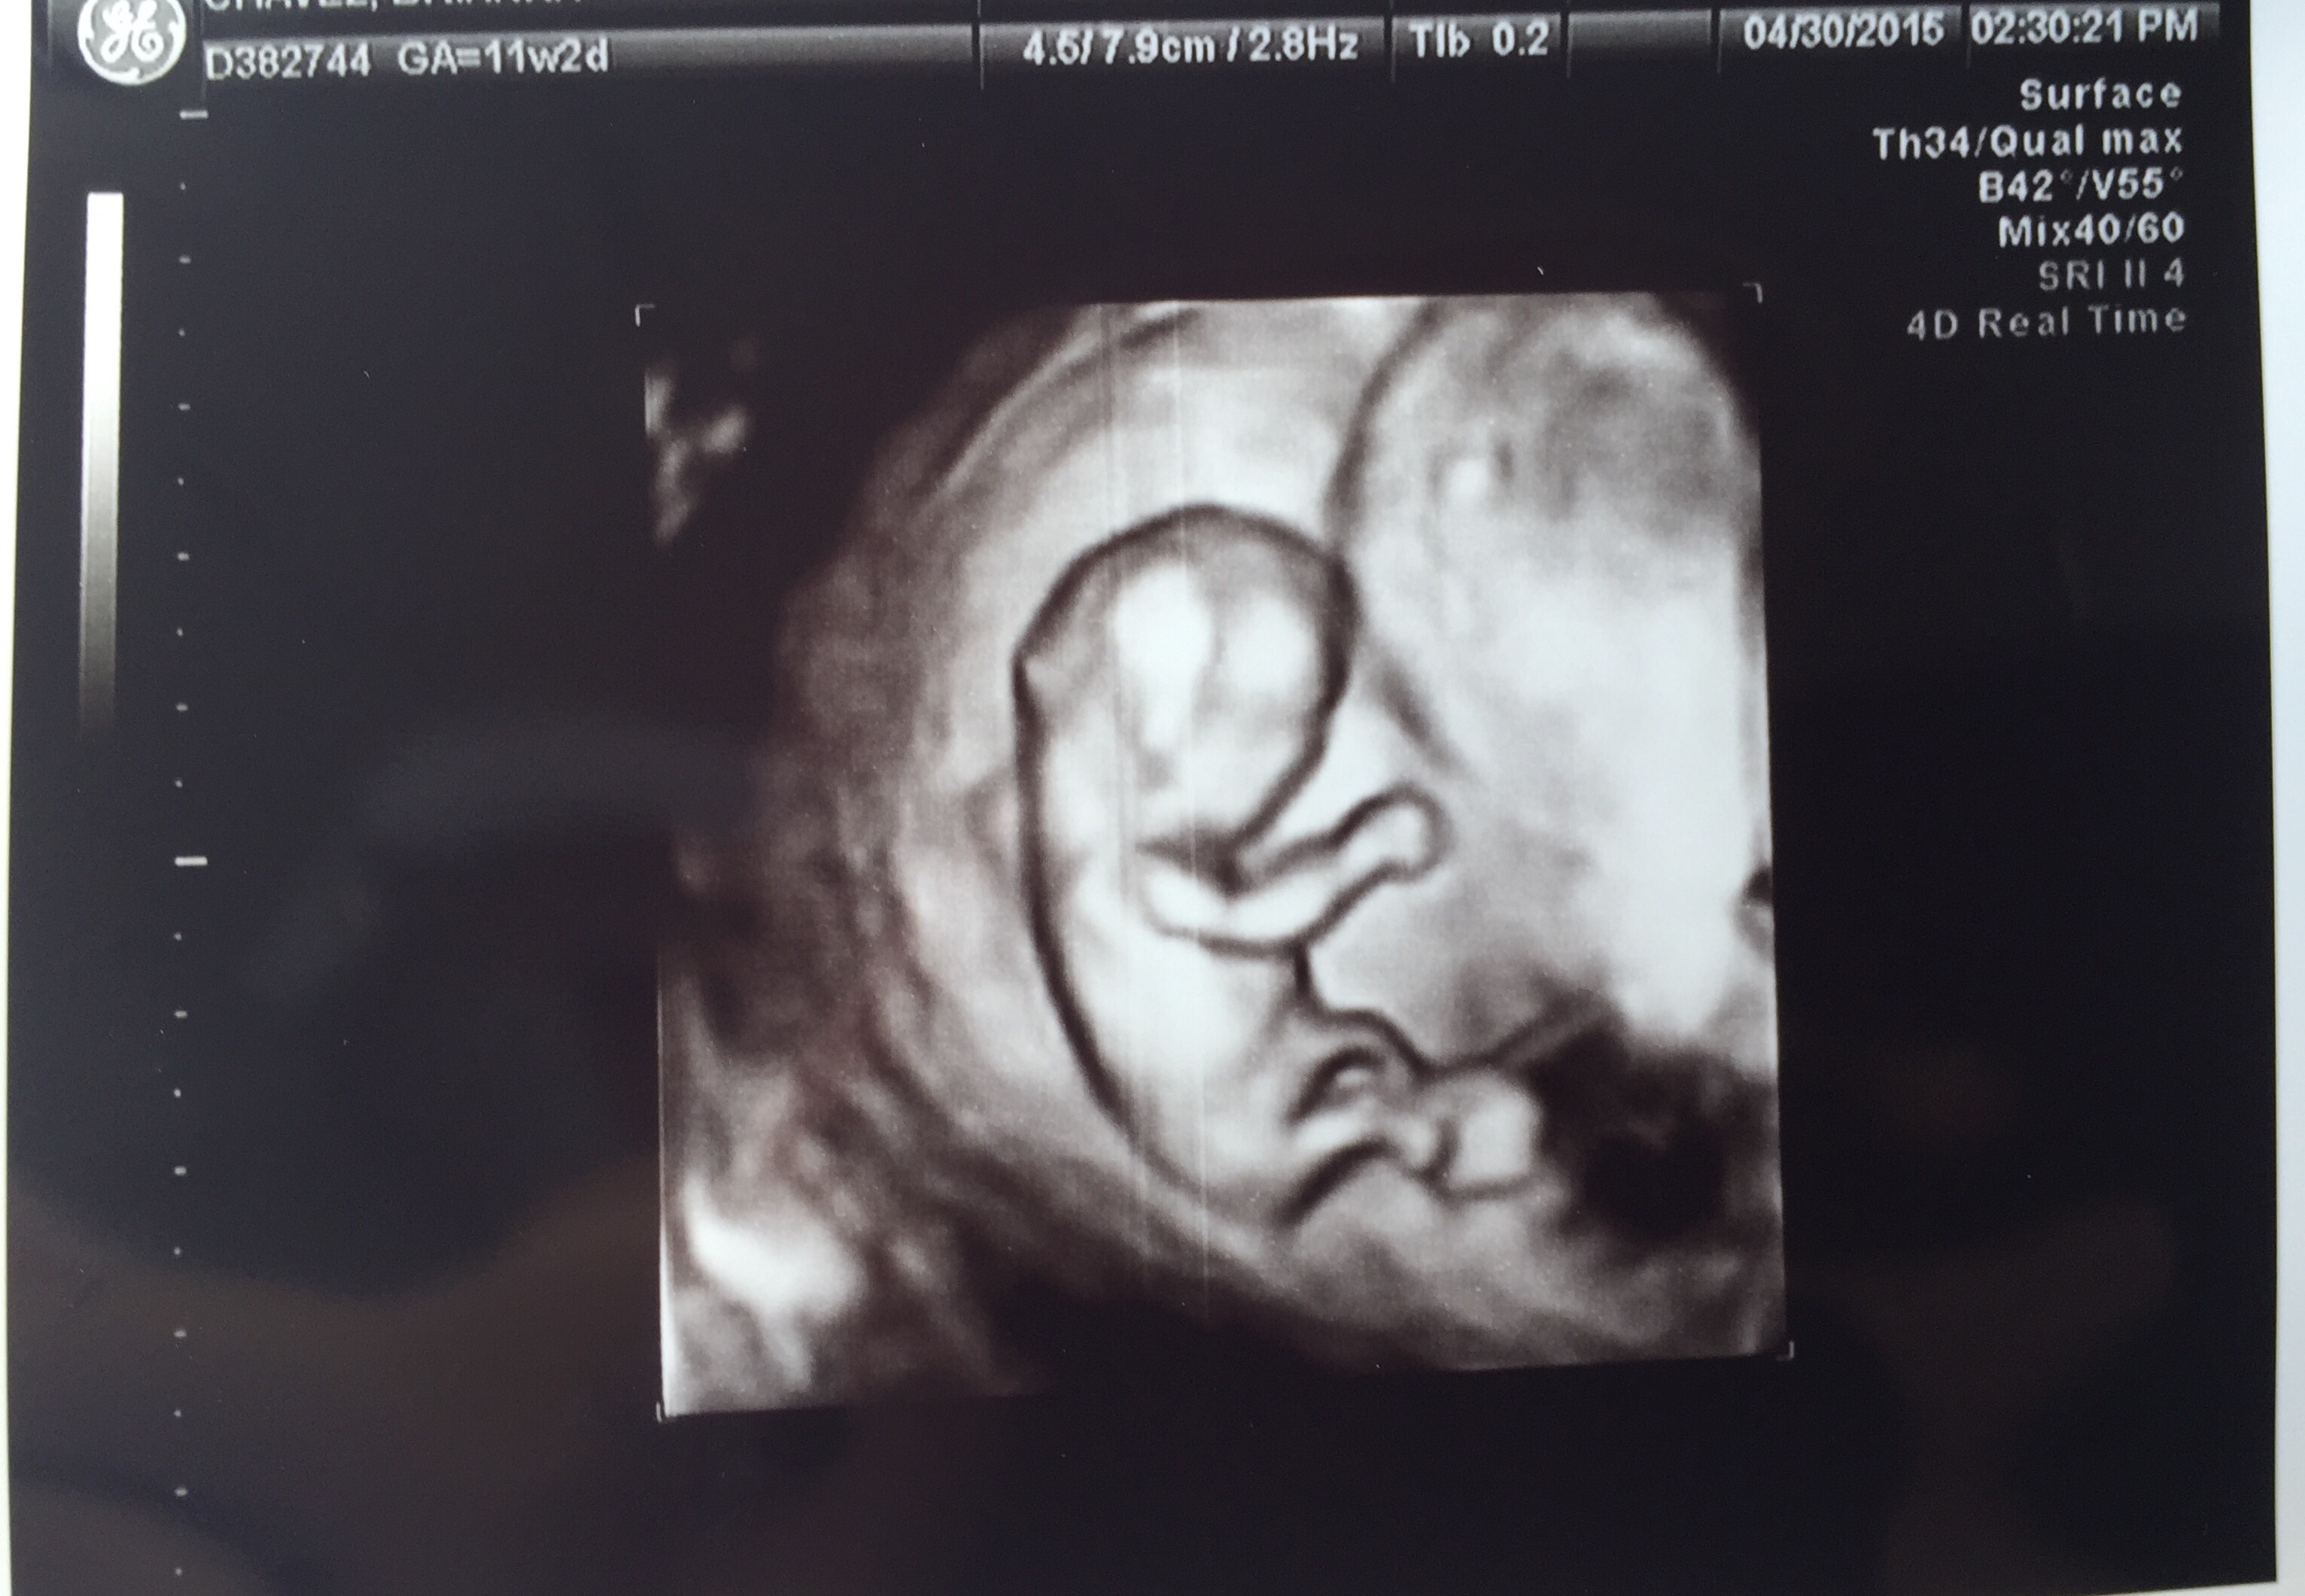

11 weeks and 2 days. This appointment was with my high risk specialist, I hope her nub theory guess was right :x so in love & super happy we got a 3d/4d.